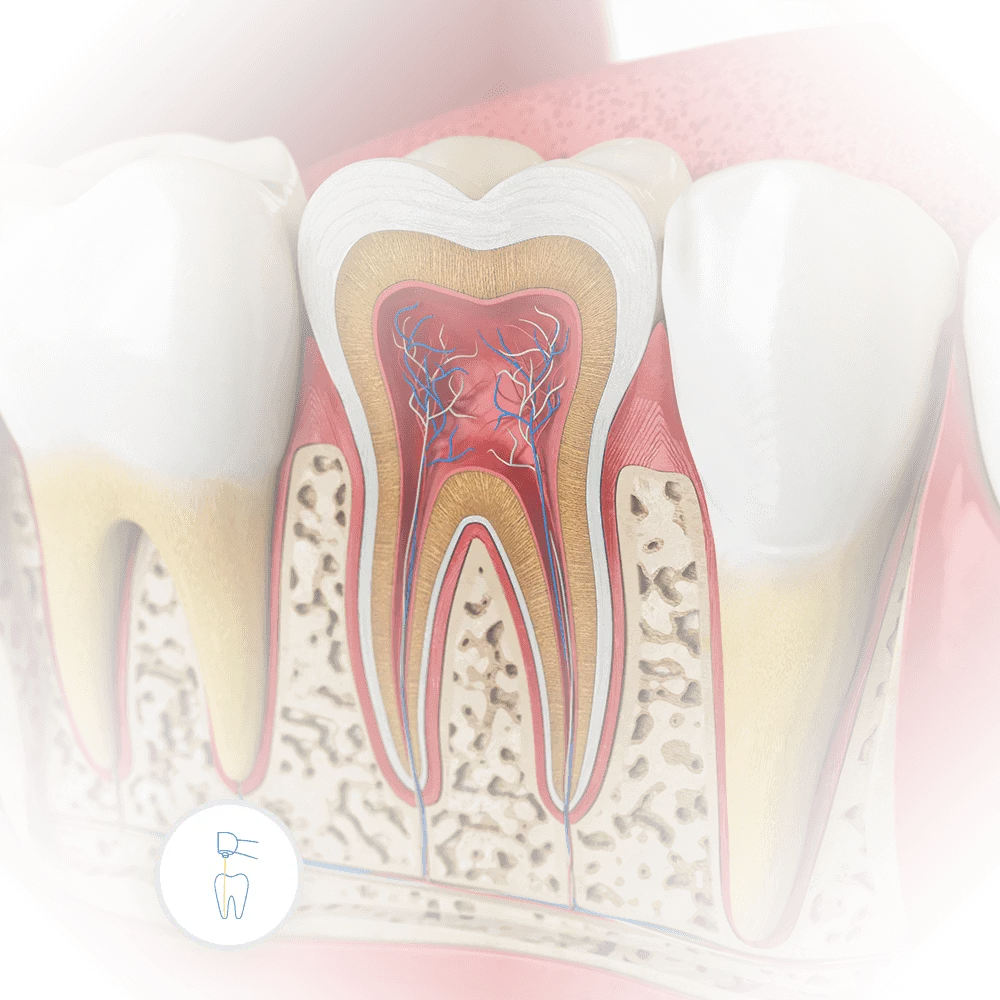

The Silent Battle: Unraveling the Realities of Gum Disease and Its Impact

A 3D visualization of a tooth set in red, inflamed gums, highlighting the critical nature of gum disease that could lead to tooth loss if untreated.

Stealthy Symptoms

Gum disease often starts quietly as gingivitis, with subtle signs like slight bleeding during brushing or mild gum redness. Ignoring these early symptoms can allow the disease to progress into periodontitis, a more severe condition that can threaten tooth stability. Catching it early is crucial to prevent more serious issues.

Risks and Ramifications

Advanced gum disease can lead to more than just discomfort or tooth loss. It’s linked to serious health issues like heart disease, diabetes, and respiratory diseases. At Vartanian Dental Group, we consider your overall health, not just your gums, to provide comprehensive care.